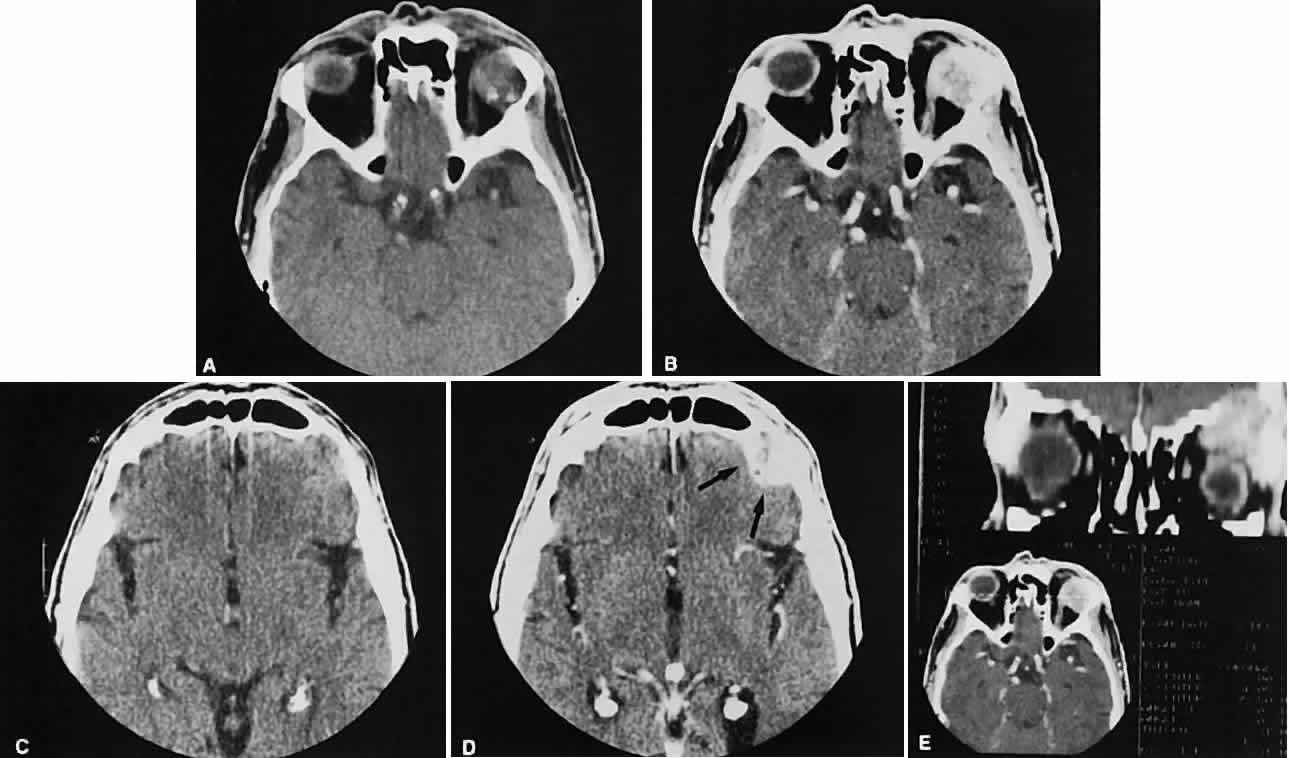

Graves' orbitopathy probably represents the most frequent cause of proptosis and EOM enlargement. The CT findings are fairly stereotyped and typically display various degrees of EOM enlargement (Fig. 7). The inferior rectus muscle usually is affected earliest, followed by the medial rectus, superior rectus, and finally the lateral rectus muscle. Rootman and colleagues13 noted more frequent involvement of the superior rectus/levator and medial rectus muscles than what had been reported previously with Graves' orbitopathy. These muscles can be affected in isolation, with the exception of the lateral rectus. To the best of our knowledge, isolated lateral rectus enlargement has not been reported in Graves' orbitopathy and in our experience usually is associated with a sphenoid wing meningioma.

Fig. 7. Graves' orbitopathy with two variations. Axial (A) and coronal (B) views show symmetric fusiform enlargement of the extraocular muscles with tapered muscle insertions. Note the predominant enlargement of the inferior, medial, and superior rectus muscles with lesser involvement of the lateral rectus muscle, a frequent pattern of enlargement in Graves' orbitopathy. Axial (C) and coronal (D) views of Graves' orbitopathy with expansion of retrobulbar ground substance and relative sparing of the extraocular muscles.

CT evidence of Graves' orbitopathy tends to be bilateral. Approximately 86% of patients with unilateral clinical findings have bilateral CT findings in our experience, which is consistent with the experience of others.42

Morphologically, the EOM belly is enlarged, with a gradual tapering toward and sparing of the tendinous portion of the muscle. Tendon involvement is a typical feature of orbital myositis. Tendon involvement helps to differentiate this lesion from Graves' orbitopathy, although Rootman and Nugent43 have noted a rare patient with Graves' orbitopathy with this finding.